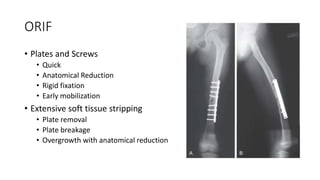

ORIF

• Plates and Screws

• Quick

• Anatomical Reduction

• Rigid fixation

• Early mobilization

• Extensive soft tissue stripping

• Plate removal

• Plate breakage

• Overgrowth with anatomical reduction